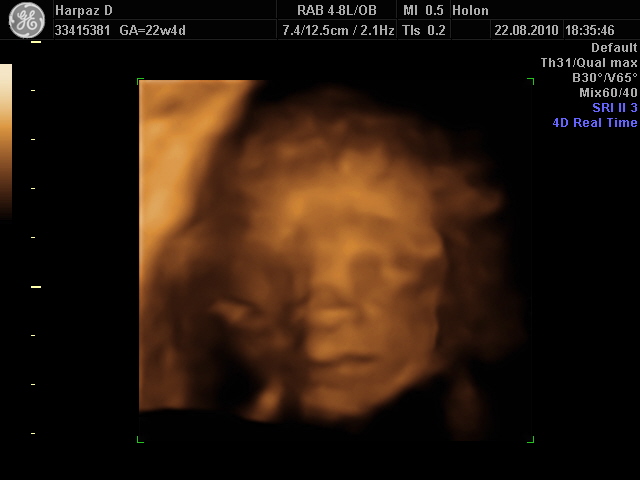

כשראינו אותך באולטרסאונד כבר התרגשנו, תמיד היית ערנית ושיתפת פעולה. וכבר אז ראו שיש לך אף כפתור חמוד שהגיע היישר מהגנים של משפחת הרפז…